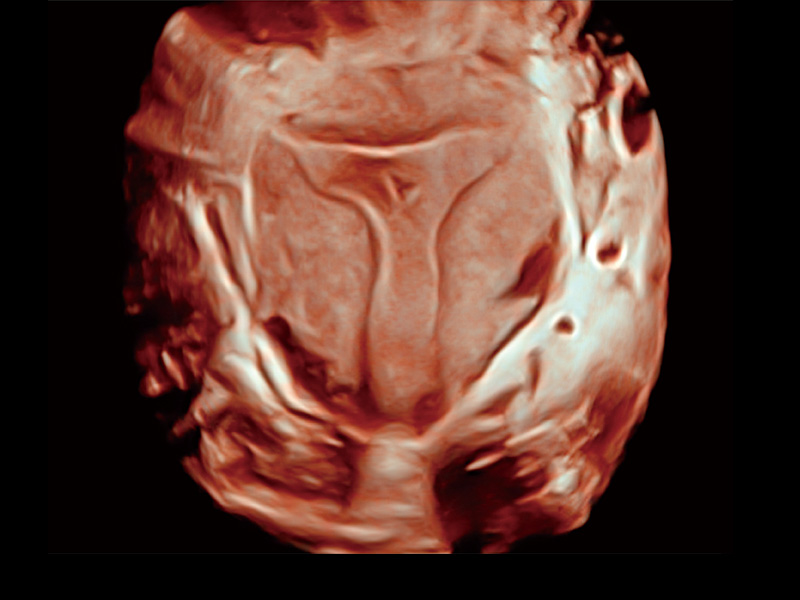

“生育问题”即关系民族复兴,也关系亿万家庭的幸福。随着婚育年龄推迟、社会压力增加等因素,越来越多人群也面临着“生不出、生不好”的问题。辅助生殖作为治疗不孕不育最有效的方法之一,也逐渐成为育儿新希望。而超声检查能为生殖需求人群的初诊评估提供宝贵的信息。 P20 Elite是开立医疗匠心打造的一款生殖应用型彩超。她继承开立医疗高端极光平台,突破性地将多款新型芯片及硬件模块进行整合,均衡了高端系统性能与小巧灵动机身。P20 Elite卓越的图像质量搭载专科探头,旨在为您提供全面的辅助生殖解决方案。

P20 Elite配备了丰富的生殖探头群和临床应用功能,在卵泡监测、穿刺取卵、胚胎移植、妊娠确认等领域,为生殖需求人群提供了新的临床机会,重新定义高端超声如何应用于生殖健康检查。